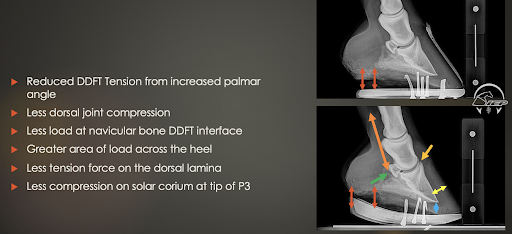

In the example of the mule-footed or club-footed upright horse, Pittman will also use a rocker shoe, but for different reasons. The problem in these cases is not leverage, but rather a deep digital flexor tension problem. A way to reduce tension, or the level of work that goes through the flexor apparatus, is possible with a rocker shoe. One complication of this type of job is that horses might have some heel soreness because of loading the heel and reducing the dorsal joint compression and navicular load. He also warns against getting the rocker too far back in these cases, because it can cause horses to stand upright on their toe and stab the toe into the ground.

The results of mechanical management with this mule-footed horse.